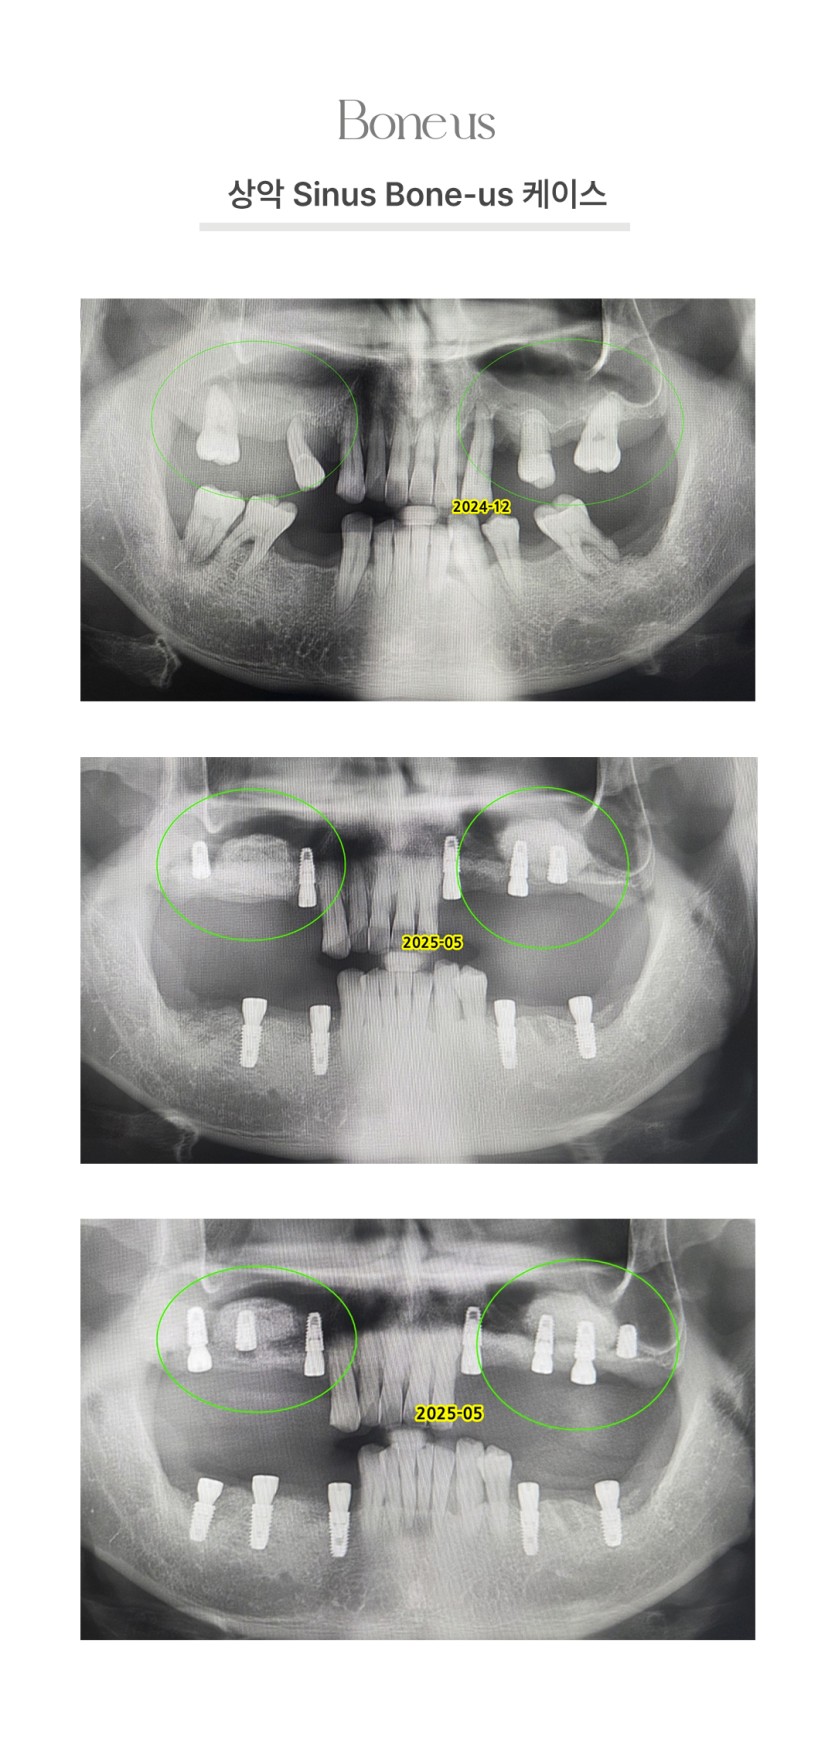

상악 Sinus 본어스 케이스